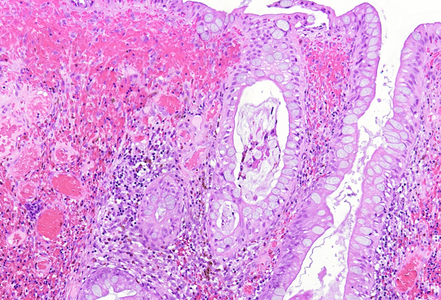

Histologically, the lesion exhibited a complex lobulated architecture (Panel A), with central cores of ramifying bands of smooth muscle extending from the muscularis mucosae into the lamina propria, configuring an arborizing pattern (Panel B). The epithelium exhibited neither cytologic nor architectural atypia and was regarded as reactive (non-dysplastic), with some glands showing dilation and distortion (Panel C). Recovering epithelium was observed on the surface, together with granulation tissue (Panel D).

Notably, the lesion demonstrated beginning pseudo-invasion, defined by the presence of misplaced benign glandular elements extending into the upper part of the stalk. There was mild inflammation of the lamina propria, abundant hemorrhage and hemosiderin-laden macrophages were also observed (Panels E-F). Immunohistochemistry for desmin and smooth muscle actin (SMA) was performed to highlight the smooth muscle fibers (compare Panel B) and emphasize the typical lobulated and arborizing architecture of this type of polyp.